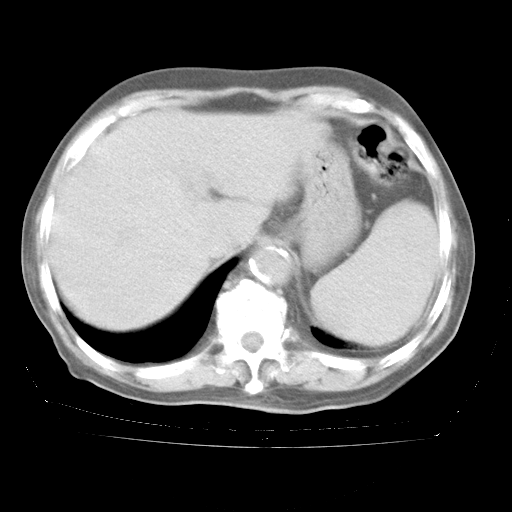

4月28日肺部CT——再次出现类似去年5月9日——透光度降低,“间质性”改变。

4月28日肺部CT——再次出现类似去年5月9日——磨玻璃样、间有“粟粒样”改变。